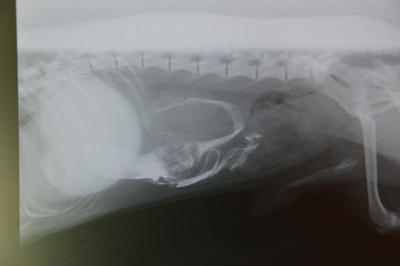

Ciało obce w dwunastnicy uwidocznione dzięki podaniu kontrastu.